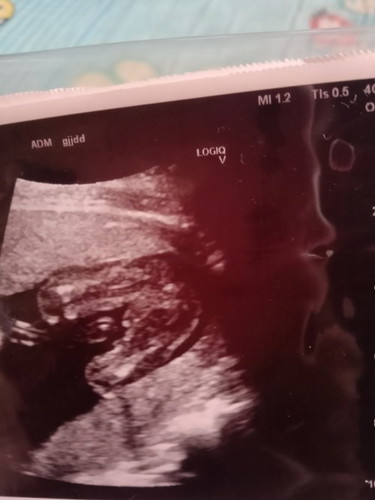

ลักษณะนี้น้องเป็นเพศชายใช่ไหมคะ

ลักษณะนี้น้องเป็นเพศชายใช่ไหมคะ ใช่กระปู๋น้องไหมคะ

อย่างชัดเลยแม่ น่าจะใช่นะคะ หมอว่าไงบ้างคะ

ผู้ชายค่ะ โด่เด่มาเลยแม่